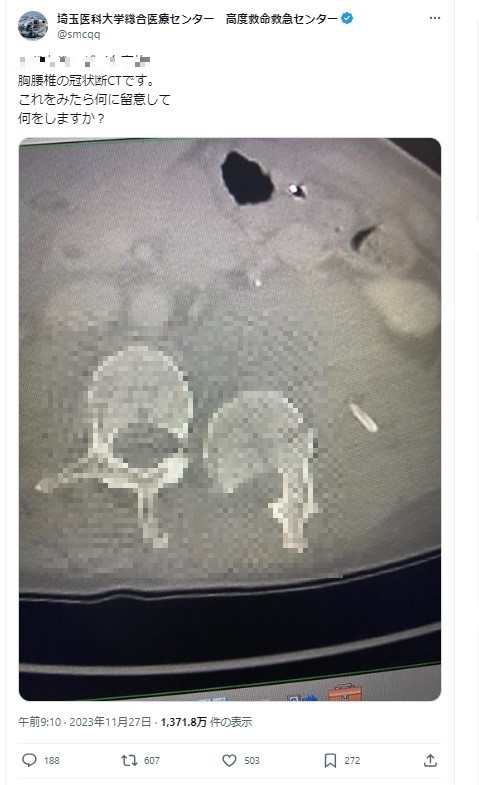

物議をかもしたのは、11月27日に投稿したCT検査の写真。性別や年代、負傷原因などを記載した上で「これをみたら何に留意して何をしますか?」と、医療関係者に問いかけるような内容でした。

実際の投稿(一部加工、現在は閲覧できず)